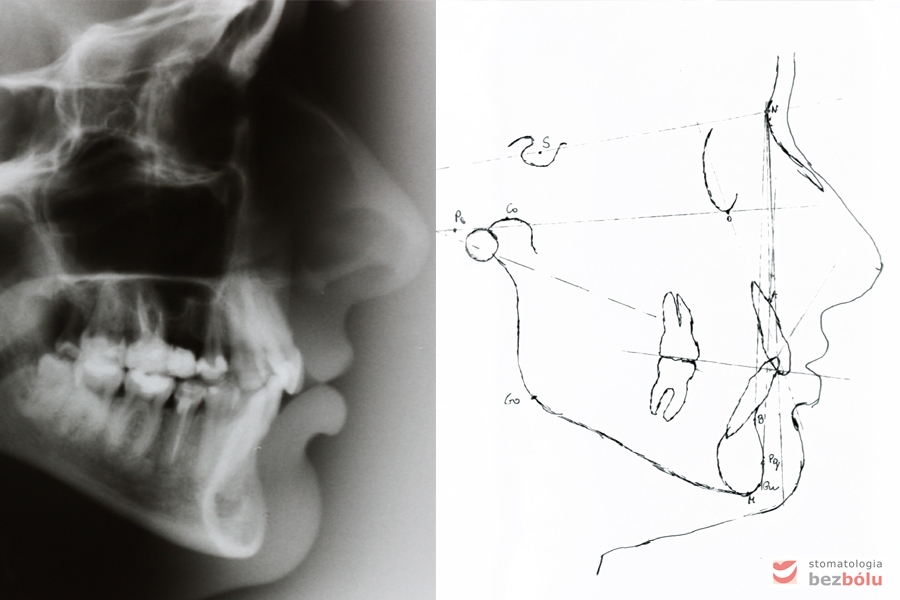

Kontrola radiologiczna - OPG

Kontrola radiologiczna – OPG

Analiza profilu twarzy wg Ricketts'a

Analiza profilu twarzy wg Ricketts’a

Analiza profilu twarzy wg Ricketts'a, prawidłowa pozycja szczęki i dotylna pozycja żuchwy względem czaszki, siekacz zbyt wychylony

Analiza profilu twarzy wg Ricketts’a, prawidłowa pozycja szczęki i dotylna pozycja żuchwy względem czaszki, siekacz zbyt wychylony